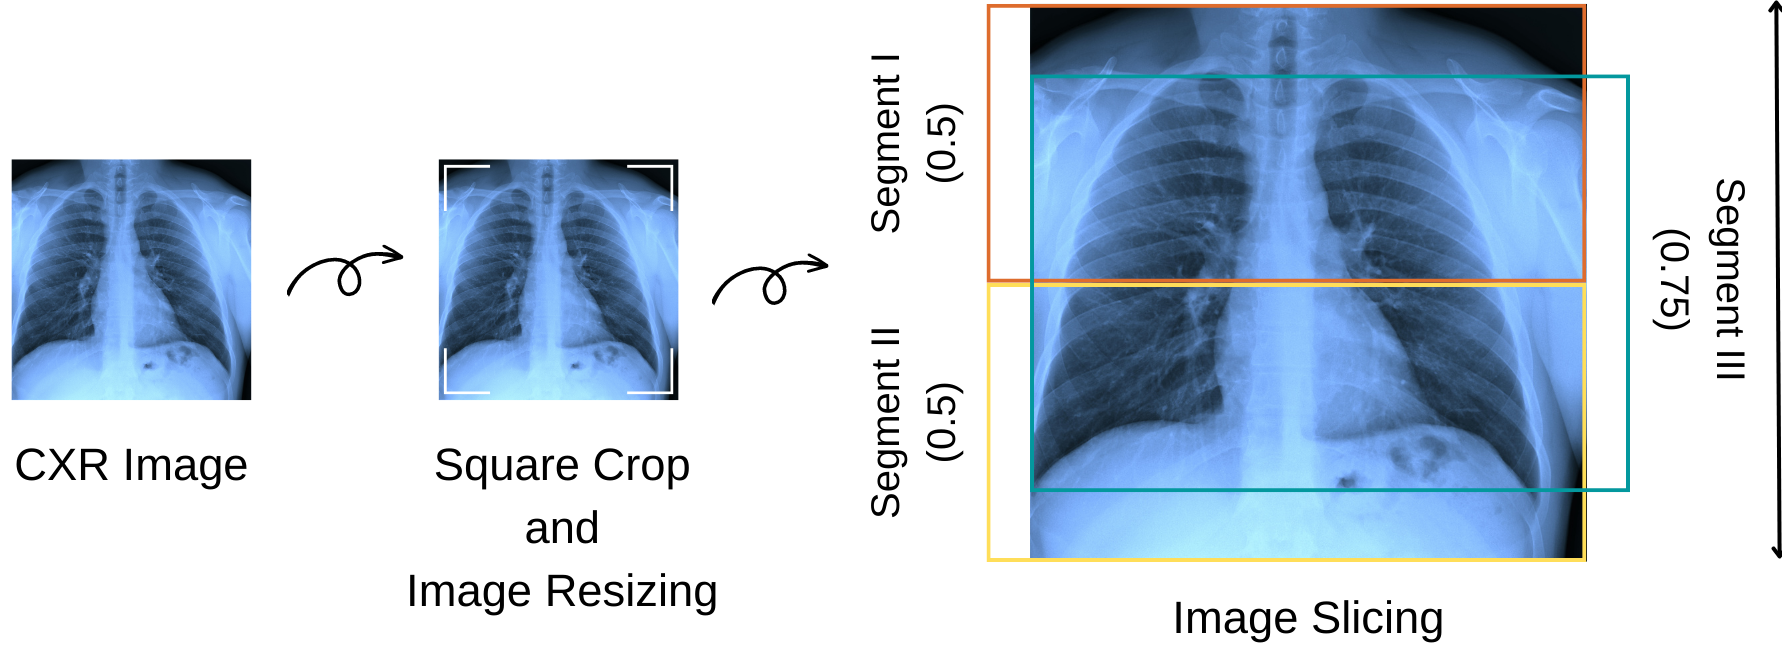

Image pre-processing is the first step of the entire process, as illustrated in Figure 2. In this step, each image is resized to 128x128 and square-cropped to ensure consistent dimensionality. Then, the image is divided into three segments (Segment I, II, and III) to reduce the amount of ”information” passed to the deep learning model in the subsequent step. Segment I covers the upper part of the lung, segment II covers the lower part of the lung, and segment III covers the middle part of the lung.